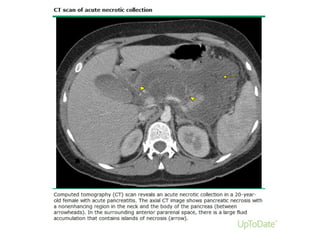

Necrotising pancreatitisNecrotising pancreatitis

About 5–10% of patients develop necrosis of the pancreatic

parenchyma, the peripancreatic tissue or both.

Necrotising pancreatitis most commonly manifests as necrosis

involving both the pancreas and peripancreatic tissues and less

commonly as necrosis of only the peripancreatic tissue, and

rarely of the pancreatic parenchyma alone.

(A) Acute necrotic collections (ANC) in a 44-year-old man with acute necrotising pancreatitis

involving only the peripancreatic tissues.

Banks P A et al. Gut 2013;62:102-111

Copyright © BMJ Publishing Group Ltd & British Society of Gastroenterology. All rights reserved.